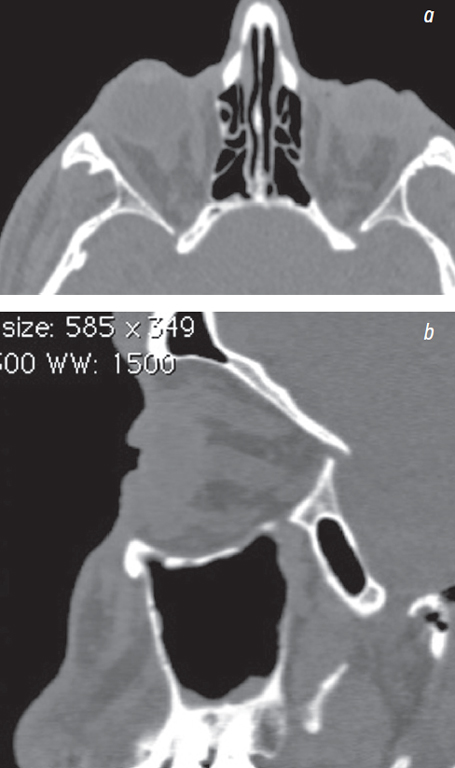

Fig. 3. Multispiral computed tomography before surgery: a — axial sections; b — sagittal sections. Socket deformity . Increased socket volume. Posstraumatic eyeball subatrophy / Рис. 3. Мультиспиральная компьютерная томография пациента до операции: a — аксиальный срез; b — сагиттальный срез. Деформация левой орбиты с увеличением орбитального объёма. Посттравматическая субатрофия глазного яблока